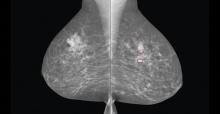

The outlook of breast cancer is changing, and death rates have been decreasing since 1989, thanks in part to treatment advances, earlier detection through screening and increased awareness.

The digital breast tomosynthesis (DBT) market has evolved rapidly within the past year, with new vendors entering the market and recent clinical data continuing to support its use. In addition, the Centers for Medicare and Medicaid Services (CMS) created dedicated reimbursement codes for DBT procedures earlier this year.